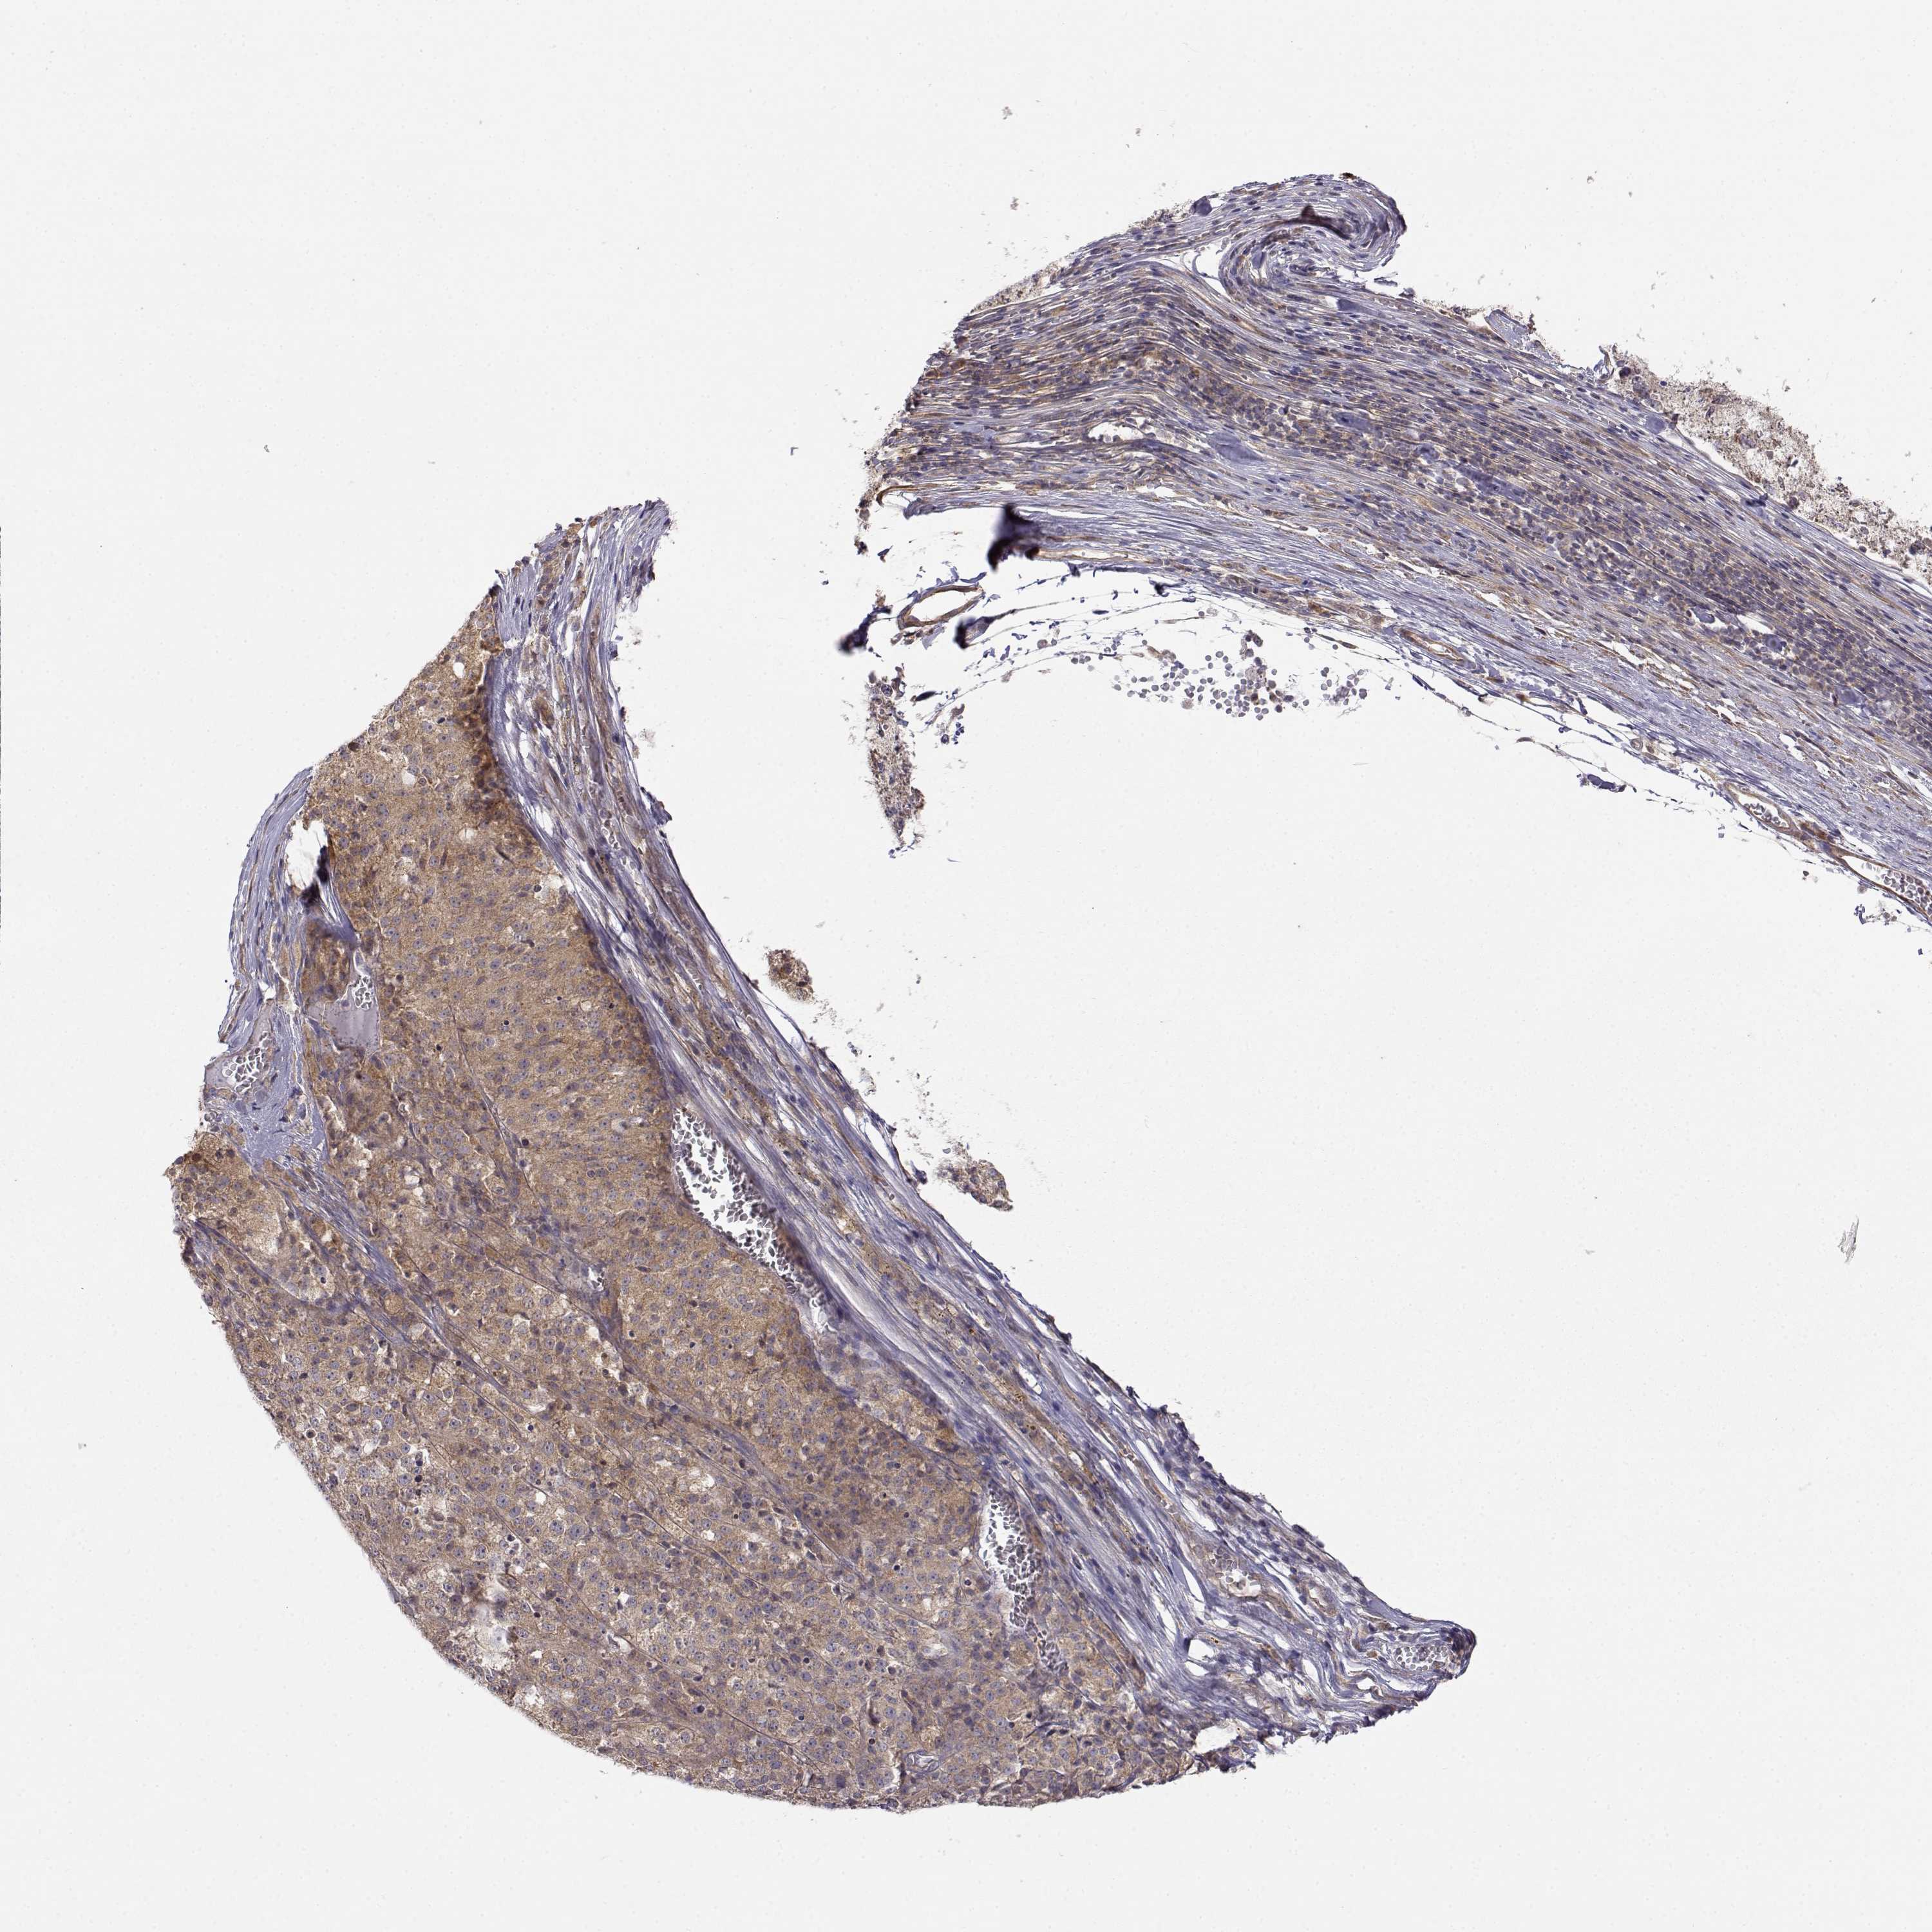

MELANOMA - Protein expressioni

A mouse-over function shows sample information and annotation data. Click on an image to view it in a full screen mode. Samples can be filtered based on level of antibody staining by selecting one or several of the following categories: high, medium, low and not detected. The assay and annotation is described here.

Note that samples used for immunohistochemistry by the Human Protein Atlas do not correspond to samples in the TCGA dataset.

Antibody stainingi

Antibody staining in the annotated cell types in the current human tissue is reported as not detected, low, medium, or high, based on conventional immunohistochemistry profiling in selected tissues. This score is based on the combination of the staining intensity and fraction of stained cells.

Each image is clickable and will lead to virtual microscopy that enables deeper exploration of all samples and also displays staining intensity scores, fraction scores and subcellular localization as well as patient and tissue information for each sample.

Antibody HPA073653

Malignant melanoma, NOS

Malignant melanoma, Metastatic site